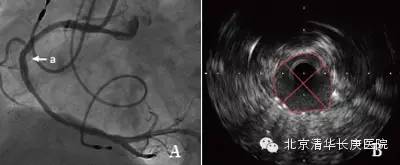

该患者于凌晨5点睡觉时突发胸痛,疼痛感向左侧肩部及后背放射,伴全身出汗以及恶心,并呕吐一次,胸口疼痛持续不缓解,由家里人送入我院急诊科,急诊科医师立即行心电图,结果提示心脏前壁、下壁、后壁心肌梗死,随后检验科回报心脏损伤标记物显著升高,急性广泛心肌梗死诊断明确,在张萍主任,缪国斌主任医师,薛亚军主治医师评估患者病情后,立即行冠状动脉造影显示冠状动脉左主干、前降支、左回旋支以及右回旋支均有广泛狭窄,情况复杂,随后在王伟民教授指导下使用血管内超声技术评估患者病变血管严重程度,并精确定位病变范围,支架大小,同时应用血管内超声技术评价支架植入后贴壁状况等,体现了我院倡导的“三精”医疗理念。术后患者平安返回病房,现病情恢复良好,胸痛症状未在发作。

血管内超声(intravenous ultrasound,IVUS) 是无创性的超声技术和有创性的导管技术相结合的一种新的诊断方法。运用该方法与传统的冠脉造影技术相结合可以准确评估血管的管壁形态及血管狭窄程度,在冠心病的介入性诊疗中有很高的指导价值。

传统冠脉造影只能显示管腔的情况,不能显示病变所在的管壁和粥样斑块,不能提供粥样斑块形态和性质的详细情况,有可能使医生低估冠脉狭窄的程度。这就使得依据冠脉造影评价冠脉粥样硬化和介入治疗疗效的准确度降低。血管内超声是利用导管将一高频微型超声探头导入血管腔内进行探测,再经电子成像系统来显示心血管组织结构和几何形态的微细解剖信息。由于超声探头直接置于血管腔内探测,因此,血管内超声不仅可准确测量管腔及粥样斑块或纤维斑块的大小,更重要的是它可提供粥样斑块的大体组织信息,在显示因介入治疗所致的复杂的病变形态时明显优于造影。